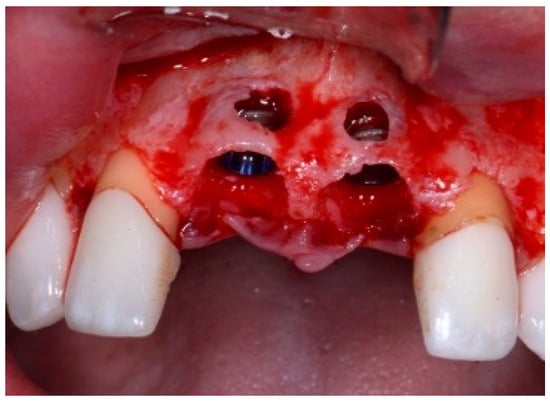

A 51-year-old male patient in good health and a non-smoker presented with a fractured maxillary canine with recurrent subgingival caries, and a failing root canal on the maxillary first premolar (Figure 18). The treatment plan consisted of the extraction of both teeth #11 and #12 roots, followed by the placement of implants. The preoperative surgical protocol described in patient 1 was followed. Figure 19 represents the residual boney defect associated with this area after implant placement. Similar to the previous cases, graft material was placed, and the area was closed for healing. Chairside temporary crowns were fabricated, followed by the placement of zirconia crowns in six months. Figure 20 represents the area three years after treatment.

Figure 18.

Clinical view of fractured tooth #11 and existing crown on tooth #12.

Figure 19.

Clinical view of implants and boney defects.